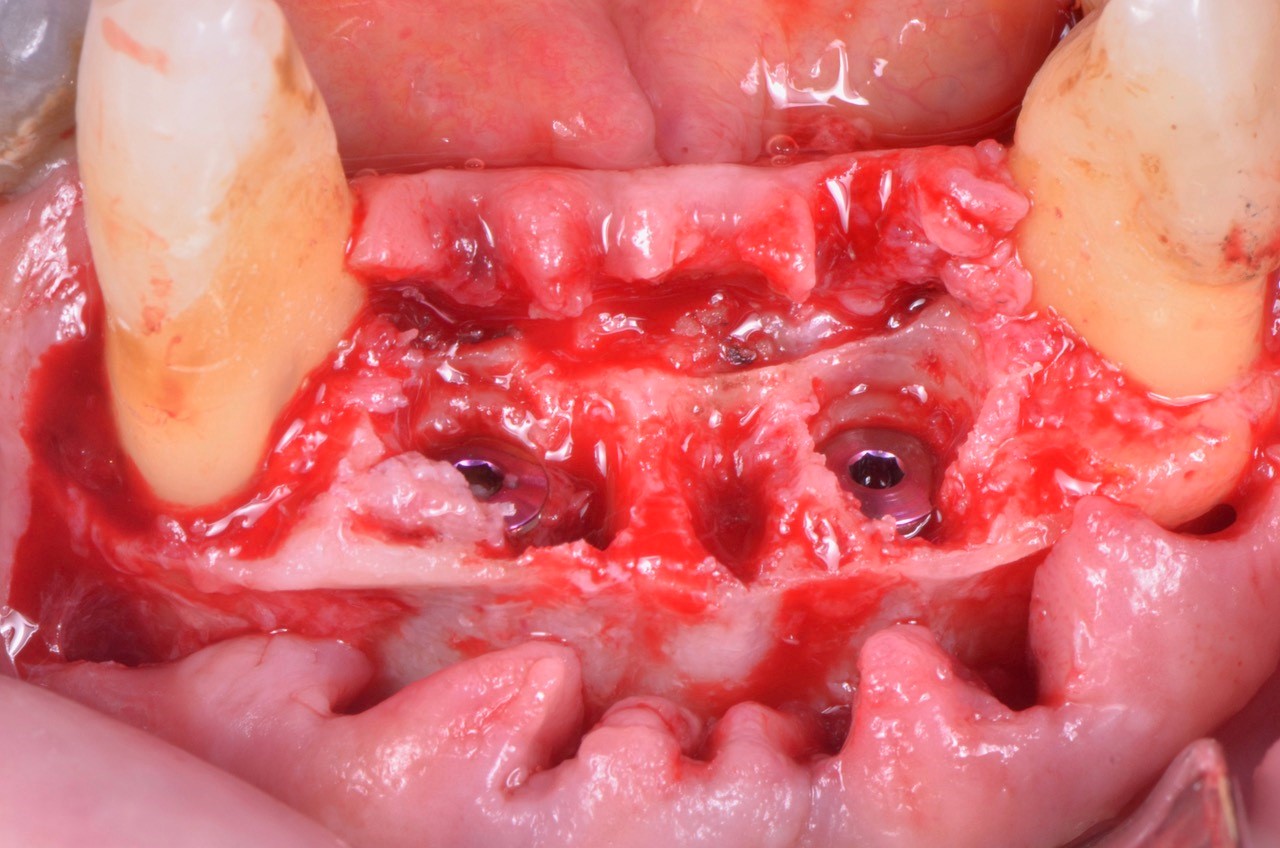

impianto-sottocrestale

Foto: impianto sottocrestale

Posizionamento sub crestale di due V3

Foto: Posizionamento subcrestale di due impianti MIS V3

Le foto di questo articolo sono state gentilmente concesse dal Dott. Federico Rivara.